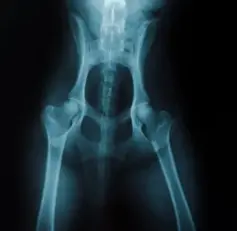

4) 진단 방법

보통 동물병원에서는 엑스레이(X-ray), 초음파, MRI 등을 통해 관절 구조를 확인합니다. 특히 전신마취 후 촬영하는 방사선 사진이 확진에 많이 활용됩니다.

강아지 고관절 이형성증은 말 그대로 고관절이 정상적으로 발달하지 못하고 불완전하게 형성되는 질환입니다. 고관절은 골반과 대퇴골(허벅지 뼈)을 이어주는 중요한 관절인데, 성장 과정에서 이 부분이 제대로 맞물리지 않으면 관절이 느슨해지고 마찰이 생기면서 통증과 변형으로 이어집니다.